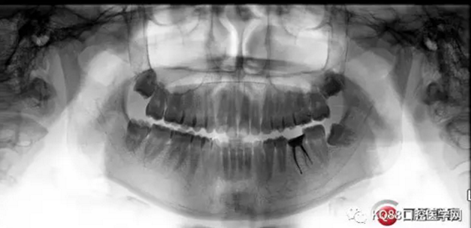

X-ray:36根尖云霧狀低密度影,根分叉未見異常。

診斷:36慢性增生性牙髓炎。

1.png

2.png